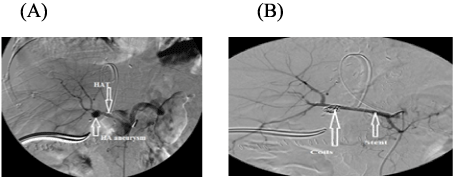

Twelve over seventeen of patients with HA stenosis were successfully managed, where 10 of them underwent late angiographic dilatation and stenting, one of them underwent late angiographic dilation and the last patients underwent late anticoagulant therapy. On the other hand 5/17 of HA stenosis cases were unsuccessfully managed where 3 of them underwent early anticoagulant therapy, one of them underwent early angiographic dilatation and coiling of GDA and the last one underwent late angiographic dilatation and stenting, however, 4 of those 5 patients died.

Figure 3: A patient with HAS underwent coiling of GDA

View Figure 3